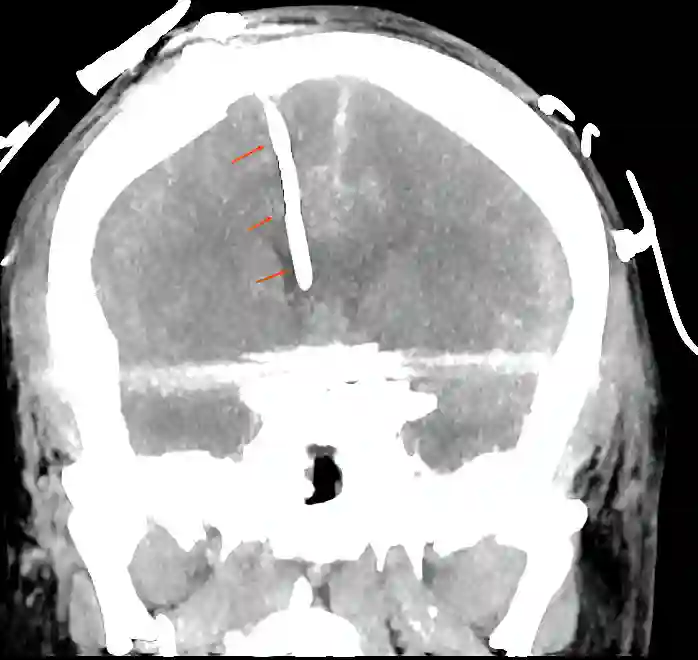

Fehllage

Eine retrospektive Studie von Toma et al.[^1] konnte 2009 zeigen, dass lediglich 40 % der "Freihand" eingelegten EVDs im ipsilateralen Ventrikel platziert worden sind. Eine größere Meta-Analyse aus dem Jahr 2023 zeigte eine Fehlplatzierungsrate von etwa 28 %[^6].

Externe Ventrikeldrainagen können zum einen im Operationssaal oder auch direkt am Patientenbett eingelegt werden. Es bestehen zwei verschiedene Arten, um eine platzierte EVD zu fixieren. Zum einen kann eine EVD über eine Tunnelierung ausgeleitet und fixiert werden oder über einen Bolt, welcher direkt in das angelegte Bohrloch eingeschraubt wird. Als üblicher Zielpunkt für die Einlage ist das ipsilaterale Vorderhorn des Seitenventrikels.